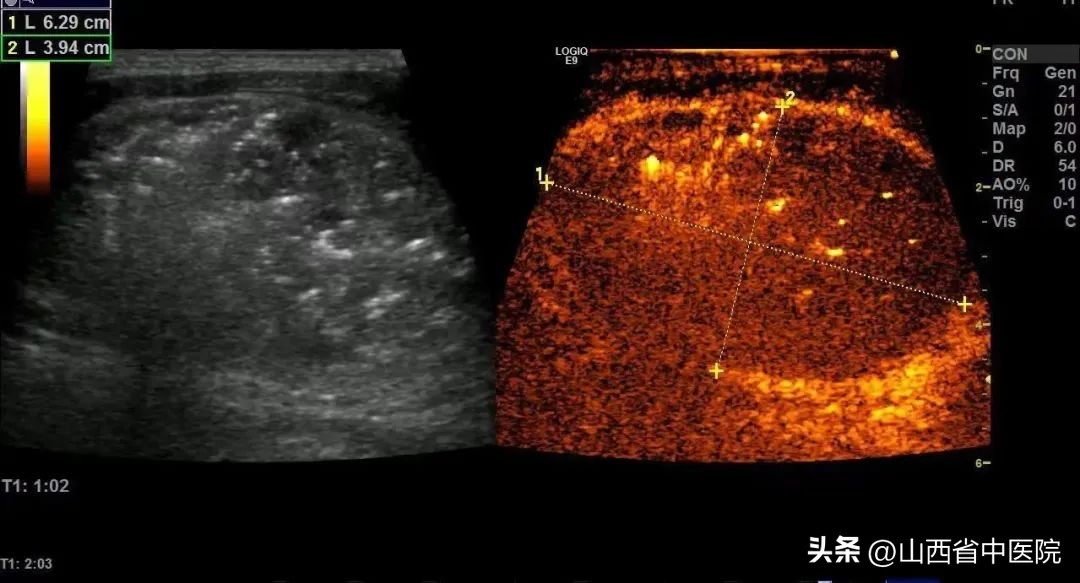

在准备充分的情况下,仅仅半小时左右时间,便完成了该手术,术后超声造影提示结节内部血供消失,消融效果满意。由于热消融脱水等原因,结节术后便明显缩小,术中及术后患者无明显不适。山西省中医院超声诊疗中心完美的完成了本次手术,同时很好的避免了并发症的发生。

(消融后造影,右侧图,结节内部无血流灌注,消融效果满意)

(结节较消融前有缩小)